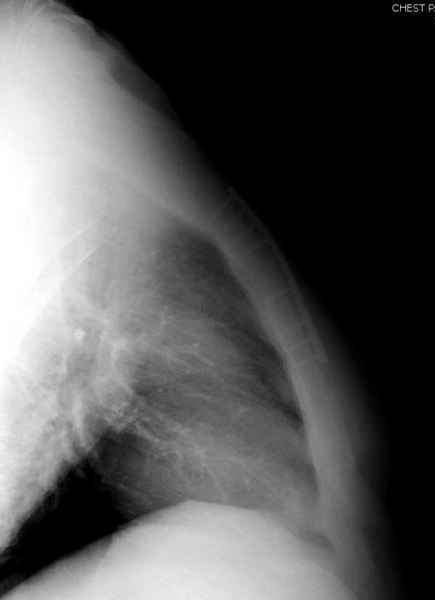

Юра, интересно, насколько такой остеосинтез контролирует степень

репозиции, а то у меня имеются снимки девочки 11 лет, направленной ко

мне на консультацию из одной республик бывшего союза.

После торакальной операции, по-видимому, сильно натянули проволоку, и

в результате получился захлест отломков в друг друга.

Оперировавший хирург предлагает подождать, а родителей беспокоит

проблема прогрессирующей ассиметрии лица, как при кривошее.

Имя     : 4 Nonunion sternum lat.jpg

Тип     : image/jpeg

Размер  : 17543 байтов

Описание: отсутствует

Url     : http://weborto.net:8080/pipermail/ortho/attachments/20090403/0de56d8e/attachment-0013.jpg